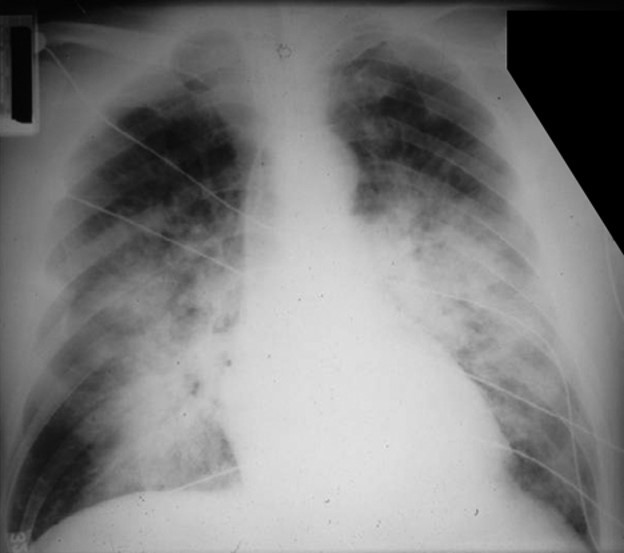

What is seen on the left?

Spontaneous Pneumothorax

(well demarcated line, right side is super black bc no lung tissue there)